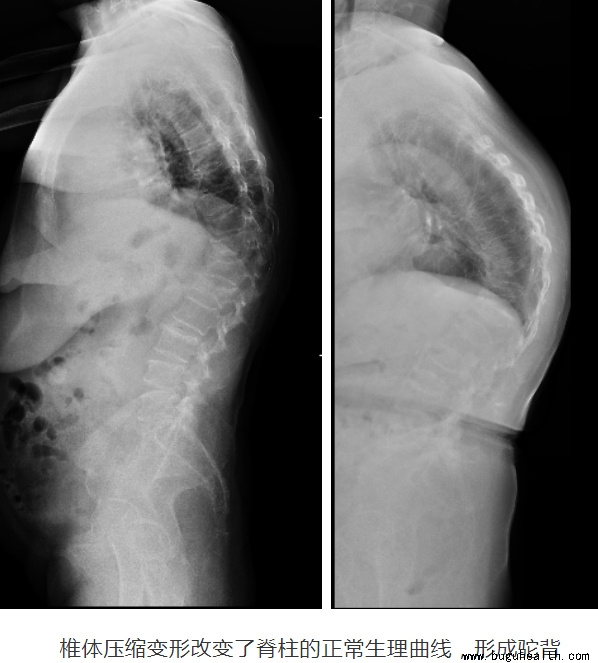

骨质疏松性椎体压缩骨折临床表现以胸/腰背部疼痛为主,伴或不伴有下肢的放射性疼痛、麻木。卧床休息时疼痛症状可减轻甚至消失,但在坐起、站立或者行走等活动时出现疼痛加重,服用一般的止痛药物不易缓解。椎体压缩严重的骨折甚至可导致脊柱出现明显的后凸畸形,表现为身高变矮和弯腰驼背。

如果骨折的骨块向后移位,压迫了脊髓和神经,出现了下肢疼痛、麻木、无力甚至大小便异常等情况时,需要尽快就医!骨折引起的椎体形变,可以造成局部的后凸畸形。单一椎体的压缩严重时可造成约30°的后凸。而由于骨质疏松影响全身,常常多个椎体均可发生压缩,这样就会形成驼背,对外观造成显著的影响。